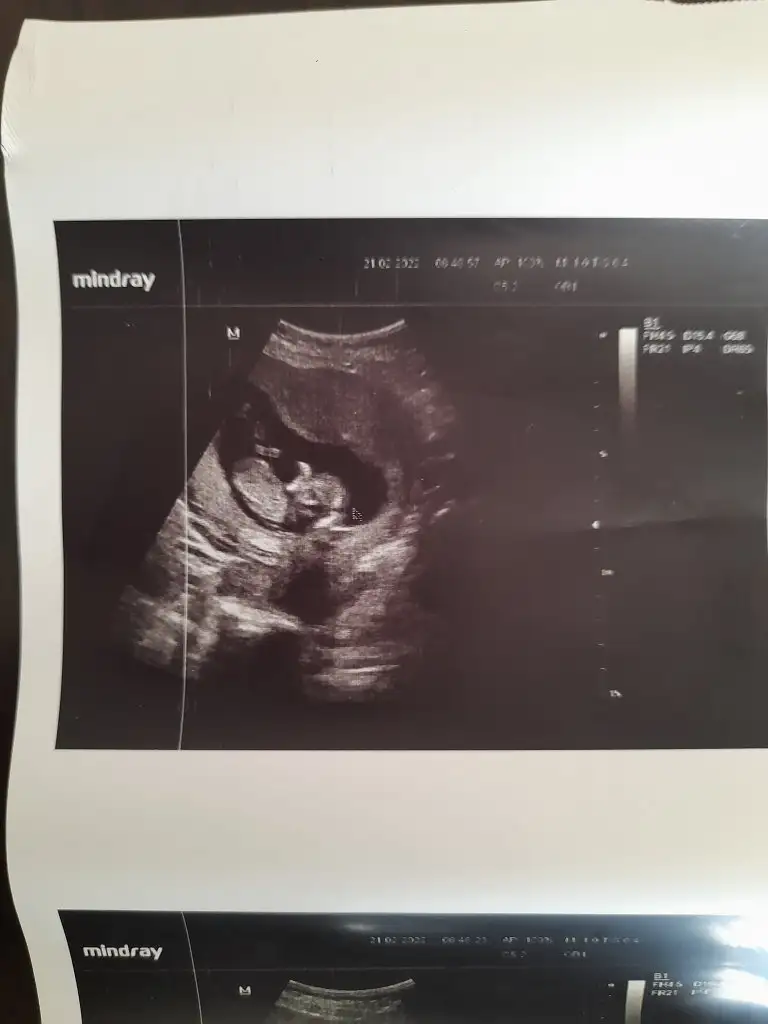

Buda diğer fotoğraf nub teorisi tahmin ıstiyorum yardımcı olur musunuz

• 20220221_100310.webp

20220221_100310.webp

18,5 KB · Görüntüleme: 73

• 20220221_092239.webp

20220221_092239.webp

26,9 KB · Görüntüleme: 67